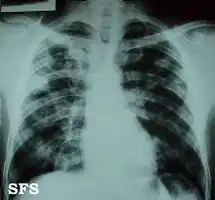

Once suspected, the diagnosis of blastomycosis can usually be confirmed by demonstration of the characteristic broad based budding organisms in sputum or tissues by KOH prep, cytology, or histology.[16] Tissue biopsy of skin or other organs may be required in order to diagnose extra-pulmonary disease. Blastomycosis is histologically associated with granulomatous nodules. Commercially available urine antigen testing appears to be quite sensitive in suggesting the diagnosis in cases where the organism is not readily detected. While culture of the organism remains the definitive diagnostic standard, its slow growing nature can lead to delays in treatment of up to several weeks. However, sometimes blood and sputum cultures may not detect blastomycosis.[17]

Chest X-ray